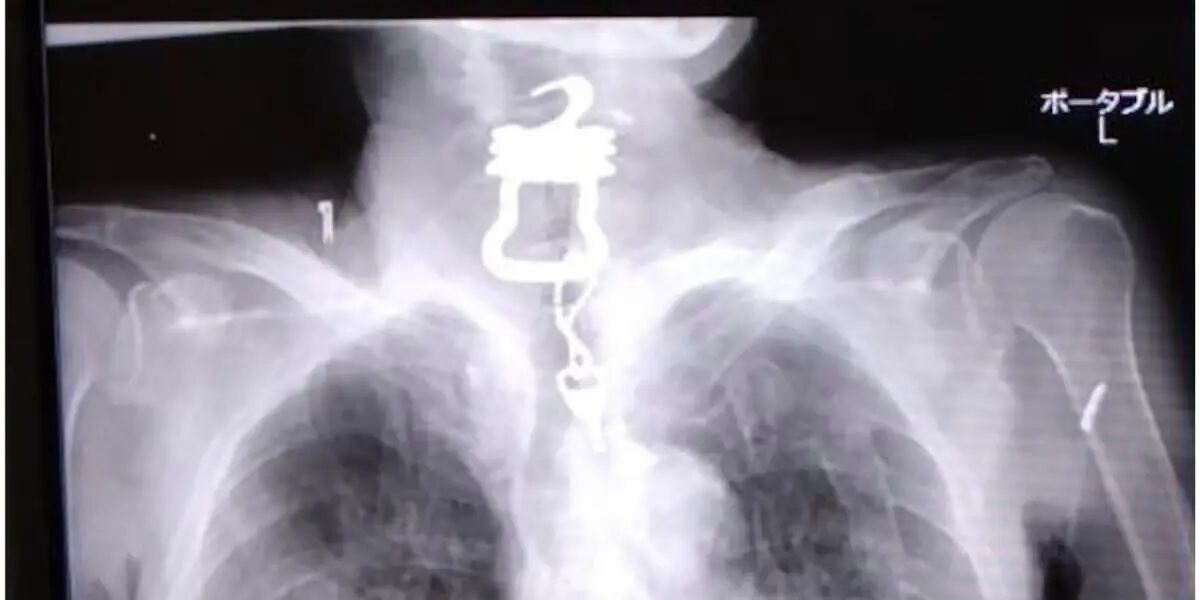

3年前、共に励ましあいながら働いていた統合失調症の兄が自死した。葬儀で20年来の友人にも障害を隠していたことを知った。自身は甲状腺がんを患い、今は生きづらさを抱えた人の「居場所づくり」に奔走している。